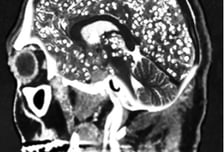

사람의 감정과 행동을 조종하는 기생충이 있다는 사실, 알고 계신가요? 기생충도 사람처럼 중추신경계가 있어 판단력을 갖추고 있는데요. 그중에서도 똑똑한 기생충으로 꼽히는 '톡소포자충'은 사람의 몸속에서 살다가 마지막 단계로 고양이 몸속으로 이동해 교배하는데, 이를 위해 숙주(사람)가 고양이를 좋아하게 만들어 고양이를 키우게 유도한다는 것으로 알려졌습니다. 해외 다수 연구에 따르면 톡소포자충에 감염된 쥐는 고양이 소변 냄새에 대한 공포감이 줄어드는 것으로 확인됐습니다. 또 톡소포자충에 감염된 남성이 그렇지 않은 남성보다 고양이 소변 냄새를 더 좋아했다는 연구 결과도 있습니다. 반면 여성 감염자는 비감염자와 별다른 차이가 없었습니다. '기생충이 몸 안에 들어오면 음식물을 대신 먹어 살이 빠질 것'이란 속설이 있습니다. 지난해 체중 감량에 어려움을 겪던 미국의 20대 여성이 기생충 알이 든 캡슐을 먹고 다이어트하려다 뇌·목·얼굴·혀·간·척추 등에 기생충이 퍼져 끔찍한 부작용에 시달렸다는 사연이 전해졌습니다.